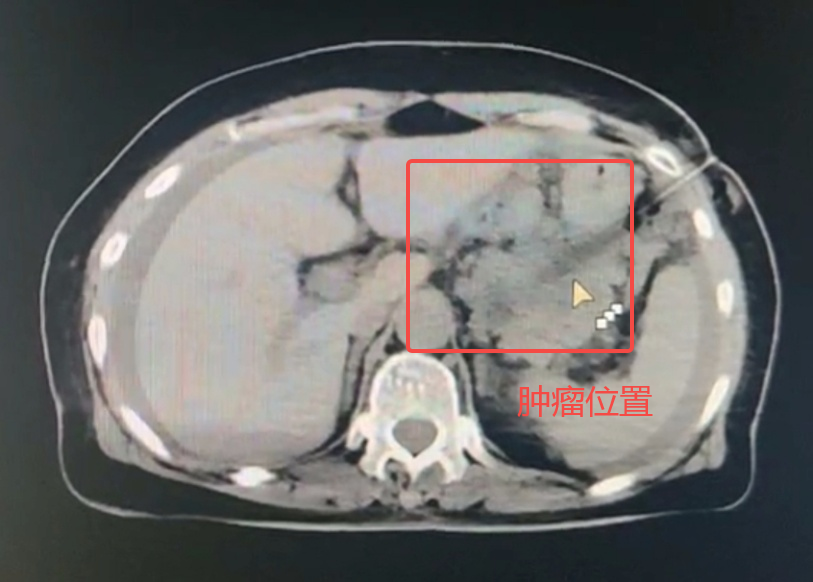

近日,泰康同濟(武漢)醫(yī)院(簡稱“泰康同濟”)腫瘤科戈偉主任團隊通過CT引導(dǎo)下胰腺穿刺活檢技術(shù),為一名72歲的胰腺腫瘤患者明確診療方向,避免了不必要的手術(shù)風險和創(chuàng)傷。作為穿刺活檢界的技術(shù)天花板,這一微創(chuàng)技術(shù)是我國每年12萬例胰腺癌新患者獲得精準治療的保障。

今年3月份,72歲的蔡奶奶因持續(xù)腹脹到某醫(yī)院就診,影像檢查顯示胰腺體尾部腫瘤性病變。4月2日,蔡奶奶轉(zhuǎn)入泰康同濟接受進一步檢查與治療。

為明確診斷,腫瘤科戈偉主任團隊果斷施行CT引導(dǎo)下胰腺穿刺活檢,采用“雙角度進針法”,先經(jīng)胃壁建立安全通道,再以18G活檢針快速獲取3條組織標本,全程僅15分鐘。穿刺后僅3天即獲得病理報告,結(jié)果確診為胰腺癌,團隊隨即采取針對性治療。